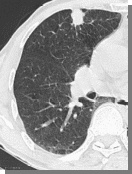

超强筛查力:AI能在秒级内扫描CT图像,精准揪出<5mm的微小结节,避免肉眼遗漏。

基于大数据训练的算法可快速筛查海量影像数据,对微小结节(<5mm)的识别敏感性高,尤其适合早期筛查。

对影像特征的定量分析(如三维重建、体积测量)更精确。